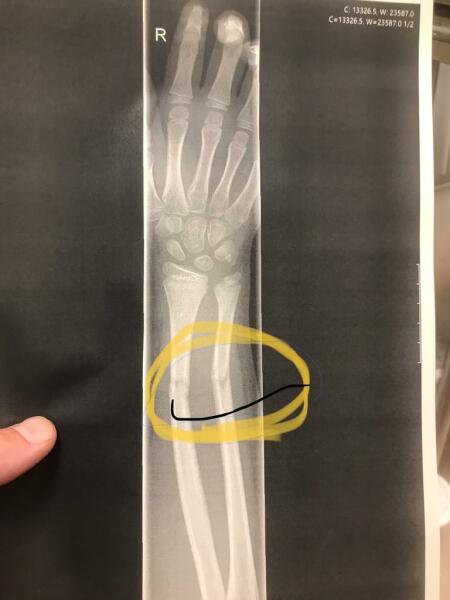

Sorry to do this but this is my daughter’s x-ray from the day she snapped both bones ( sorry anatomy not my thing!) on her trampoline. She was in awful pain and had to have her arm re-broken and set in theatre. It didn’t ruin our Summer but it certainly had an impact. I have never seen our trampoline in the same way again. If you do get one, I would say that your DC are not allowed to do ‘flips’.

@Lovemybunnies wow! Hope she made a full recovery